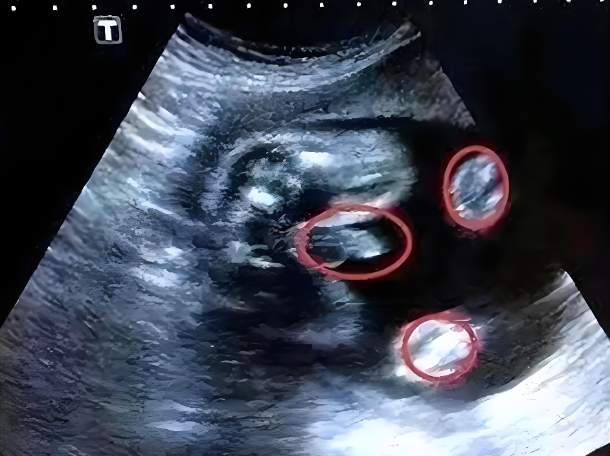

肾盂是肾脏收集尿液的部位,正常情况下,尿液会从肾盂经输尿管流入膀胱。肾盂分离指的是超声检查时发现肾盂前后径增宽,肾盏与肾盂之间的连接部出现间隙。这一表现提示尿液在肾盂内积聚,导致局部扩张。

在孕期超声检查中,肾盂分离的测量通常以毫米为单位,不同孕周的正常参考值有所差异。轻度分离可能是生理性的,重度则需警惕病理性问题。

医生会根据孕周判断分离是否在正常范围内。例如,孕20周前肾盂前后径小于4毫米多为正常,20至30周小于7毫米通常无大碍,30周后小于10毫米也常视为生理性。